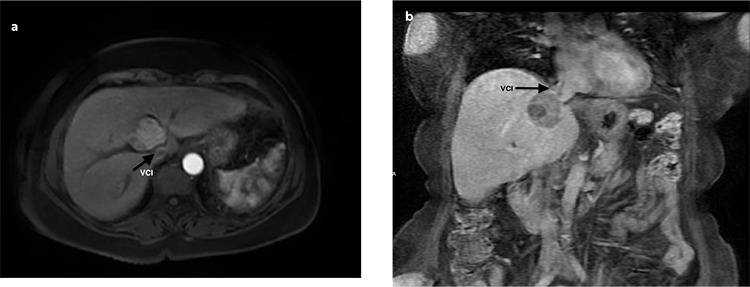

Methods: Between January 2019 and January 2022, percutaneous MWA procedures were performed for 50 liver tumors. These lesions were situated in close proximity to anatomically essential structures, with a maximum distance to surrounding structures being 10 mm. Because of comorbid lung diseases, patients could not undergo deep anesthesia. Regular follow-ups were performed using blood tests and dynamic contrast-enhanced computed tomography or magnetic resonance imaging.

Results: The patient cohort consisted of 30 (68%) men and 14 (32%) women, with a mean age of 64.36±11.65 years (range: 40-80 years). The lesions were challenging to access and were located in proximity to critical structures such as the diaphragm (32, 64%), gallbladder (8, 16%), major vessels (5, 10%), and heart (5, 10%). During the follow-up period, 10 patients (23%) had local tumor recurrence and 14 (32%) had new primary foci in a different location and metastasis [liver (10) and non-liver organs (4)]. No major complications developed, and 21 of 44 patients experienced minor complications, which were treated with local medications during follow-up.